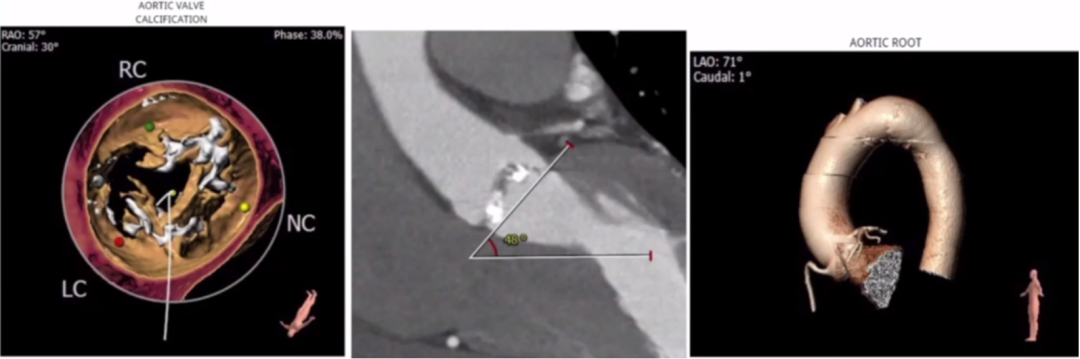

CT评估:

瓣环周长83.5mm,平均直径26.6mm,左室流出道周长85.5mm,平均直径27.2mm,升主动脉直径37.3mm,STJ直径33.3mm,左冠高度12.7mm,右冠高度14.7mm。

瓣环结构:瓣环底部有钙化,延伸至流出道,为功能性二叶瓣;右无及左无交界有明显钙化融合,右无更严重,角度48°,钙化积分815.9mm。